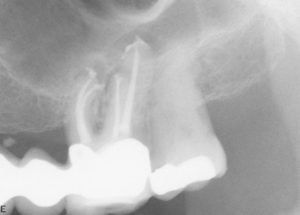

Root Canal / Retreatment

Apical Microsurgery / Apicectomy

Clinical Cases